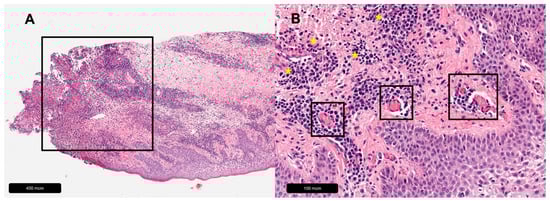

Figure 5.

Pyoderma gangrenosum. (A) Overview, black rectangle = massive leukocyte infiltration. (B) Magnification, yellow asterisks = leukocyte infiltration, black rectangles = perivascular lymphocytic infiltrates with associated fibrin thrombi suggestive of secondary vasculitis.